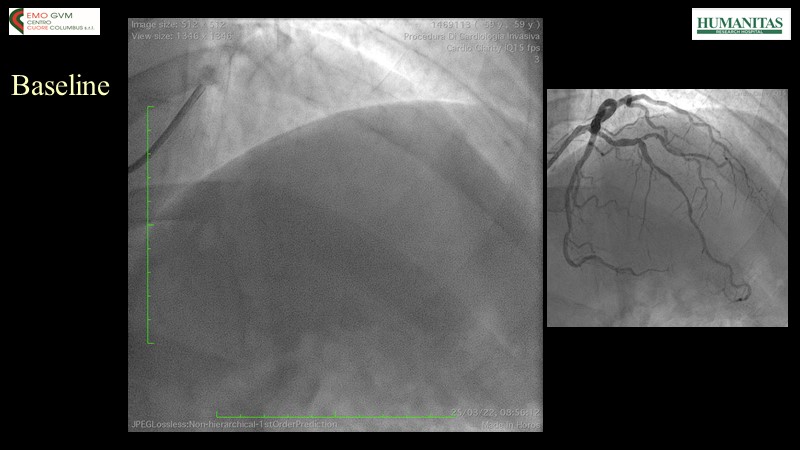

- To know why sirolimus coated balloon is the ideal choice in native vessel disease treatment through a case presentation